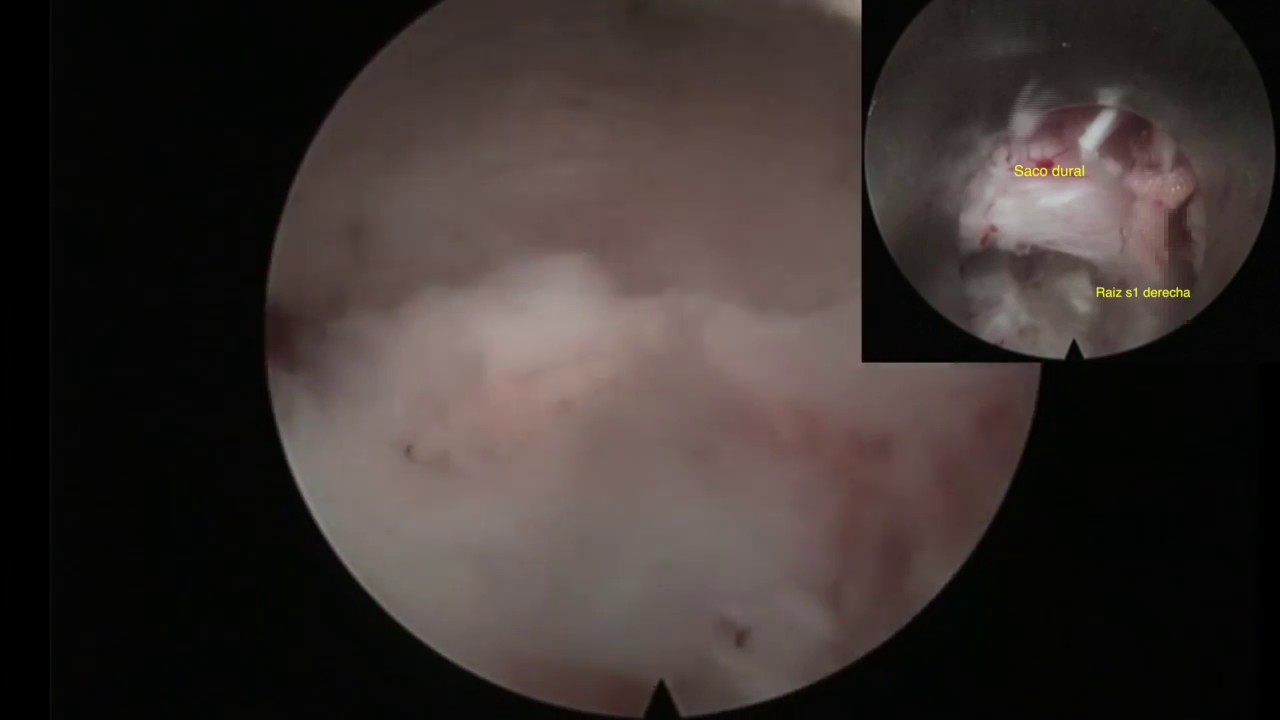

DISCECTOMIA ENDOSCOPICA TRANSFORAMINAL Esta técnica quirúrgica avanzada permite liberar las raíces nerviosas aprovechando un espacio anatómico como es el foramen. - Con la discografía previa, se tiñe el disco y la hernia de azul, permitiendo un fácil reconocimiento de las estructuras. - El post operatorio es muy favorable, aunque es recomendable el uso de una faja lumbar por un tiempo determinado, se esa forma se reduce la posibilidad de recidiva(una nueva hernia).